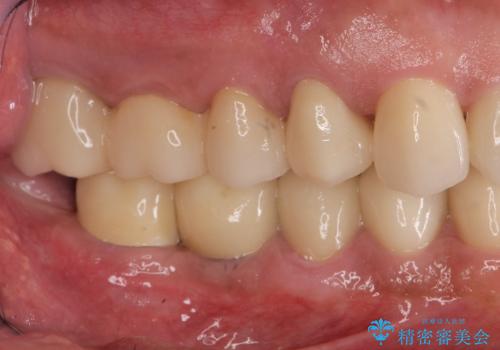

多数の銀歯と虫歯、セラミック・インプラント治療

- 銀歯だらけの口腔内を全てきっちり治療したい、と希望され来院されました。

検査の結果、残すことの難しい歯をインプラントに置き換え、残すことのできる歯は虫歯の徹底的な除去後にセラミック治療を行っていくこととしました。

- 125万円(インプラント×2・チタンカスタムアバットメント×2・ジルコニアクラウン×4・仮歯×4)費用は治療当時の料金となります

銀歯が口腔内からなくなり審美的になっただけでなく、歯ブラシのしやすさや噛み合わせの安定、口臭の減少など、良好な結果を得ることができました。